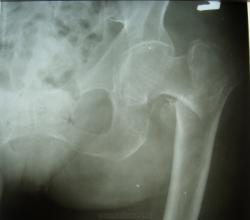

Для исключения повреждения лонных костей - Rg-контроль...

похоже что с лоными все в орядке в отличии от шейки бедра

возможно, газы смутили (и остеопороз знатный)...

почему то был уверен, что лонная кость сломанаю